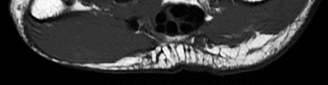

Question 22:

A 54-year-old male with a history of intravenous drug use presents with severe back pain, fever, and progressively worsening bilateral lower extremity weakness over the last 48 hours. A representative MRI is shown below. Given the classic findings for this pathology, what is the most likely causative organism, and what is the standard definitive treatment?

Correct Answer: Staphylococcus aureus; urgent surgical decompression and targeted antibiotics

Explanation:

The clinical scenario and presumed MRI findings (epidural fluid collection causing cord compression) are classic for a spinal epidural abscess. The most common causative organism overall, and specifically in intravenous drug users, is Staphylococcus aureus. Because the patient is exhibiting progressive neurologic deficits (lower extremity weakness), urgent surgical decompression (usually a laminectomy) combined with targeted intravenous antibiotics is the standard definitive treatment to prevent permanent neurologic injury.